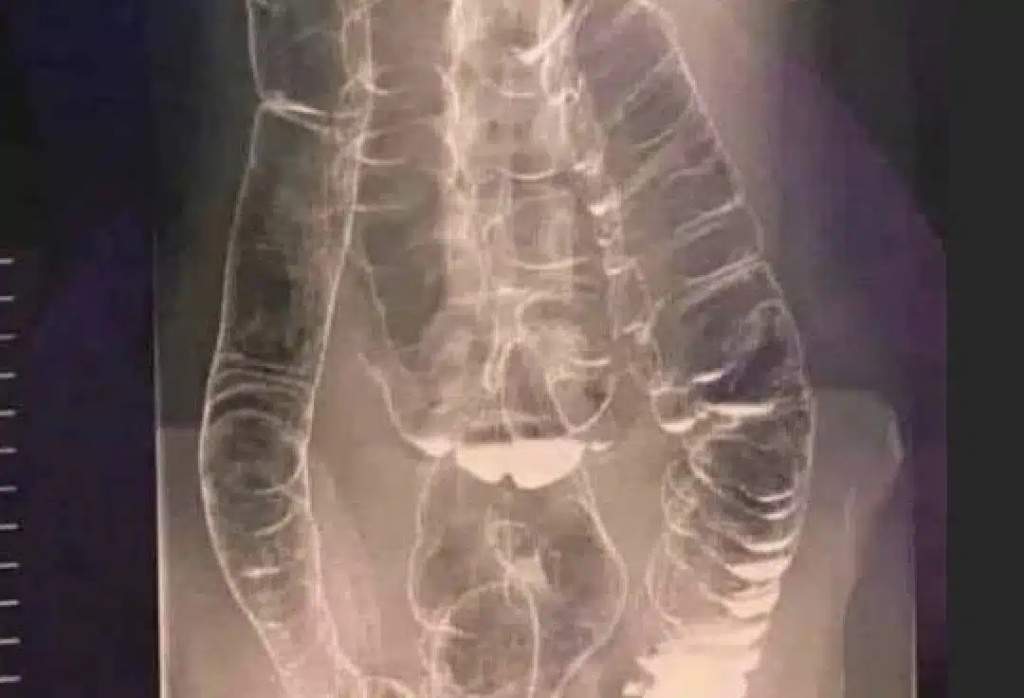

Χρόνια δυσκοιλιότητα – Μια σιωπηλή απειλή για την υγεία του πεπτικού συστήματος